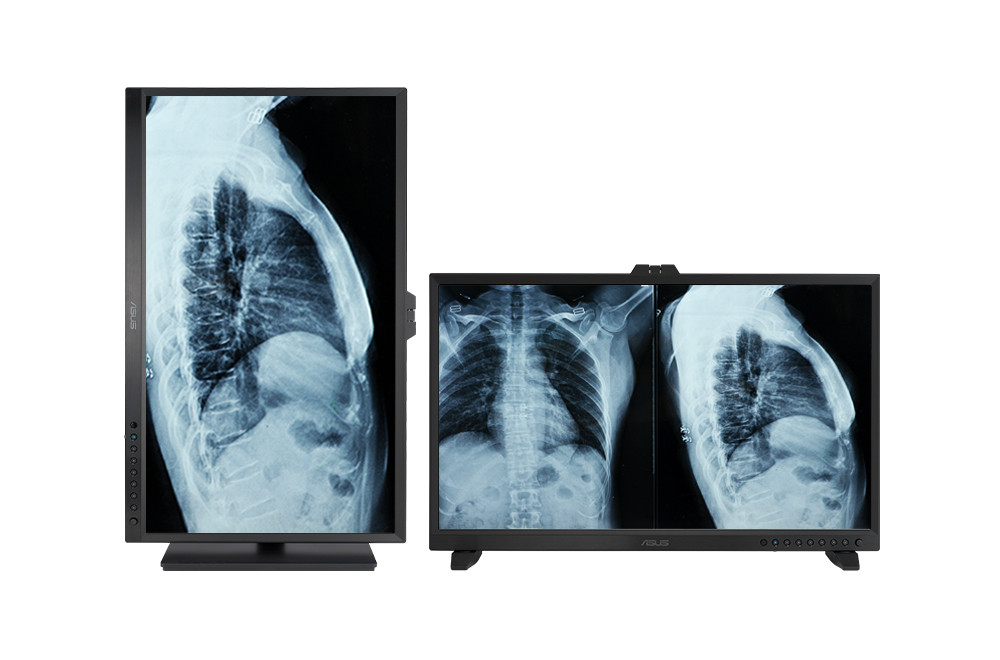

ASUS HA3281A 32″ 0.1ms 60Hz HealthCare 4K Ultra HD IPS Monitör

ASUS HA3281A 32″ 0.1ms 60Hz HealthCare 4K Ultra HD IPS Monitör

ASUS HA3281A 32" 0.1ms 60Hz HealthCare 4K Ultra HD IPS Monitör

- Konforlu izleme deneyimi için eğme, döndürme, dik çevirme ve yükseklik ayarı ile ergonomik tasarım

- Yan Yana Resim (PbP): Farklı kaynaklardan gelen görüntüler ekranda yan yana koyularak aynı anda iki veya dört farklı ayar görüntülenebilir, her pencerenin renk ayarı sRGB, DICOM, Kullanıcı Modu 1 veya Kullanıcı Modu 2 şeklinde yapılandırılabilir.

- Resim İçinde Resim (PiP): İkinci kaynaktan gelen görüntüyü, pencere halinde ekranın bir köşesine kolayca konumlandırabilirsiniz.